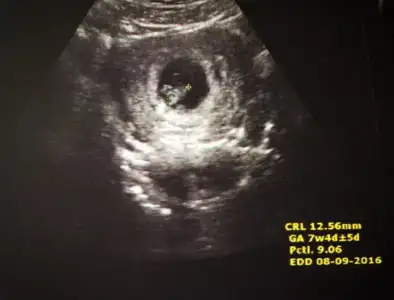

Iste benim mucizem

Eklentiler

• 20160128_141212.webp

20160128_141212.webp

21,3 KB · Görüntüleme: 226